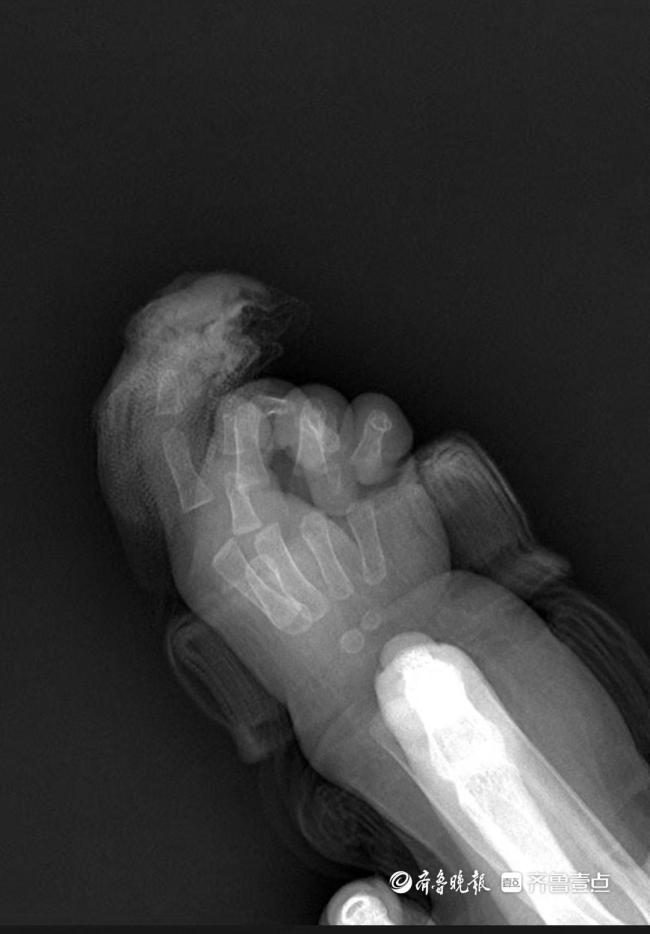

急诊就诊时间是9时22分,同步启动术前准备。手及上肢外科主治医生王思月回忆,急诊团队第一时间为芙芙止血、抽血、做心电图和拍片,“孩子伤口还在渗血,更换了3次纱布,同时输液,避免脱水。”

手术是4月4日下午1点开始的,5点前结束,历时3个多小时。为小婴儿接上断指部位的血管和神经是显微镜下的极限挑战。最困难的是血管太细,直径不足0.5毫米,仅为成人的1/5。王思月需用比发丝还细的显微缝线,在20倍显微镜下精准缝合6-8针,间距误差不能超过0.1毫米,神经和肌腱也得一一吻合,还有细如牙签的钢钉固定指骨,不能损伤骨骺板。